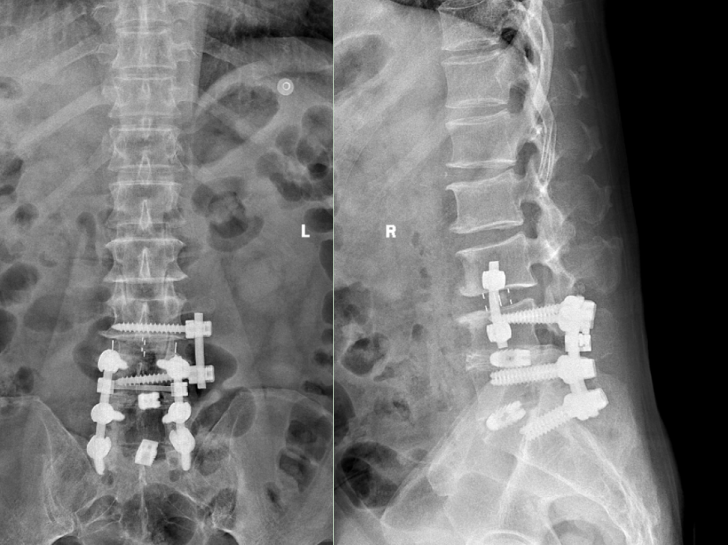

術后復查x光片提示腰椎內固定位置良好